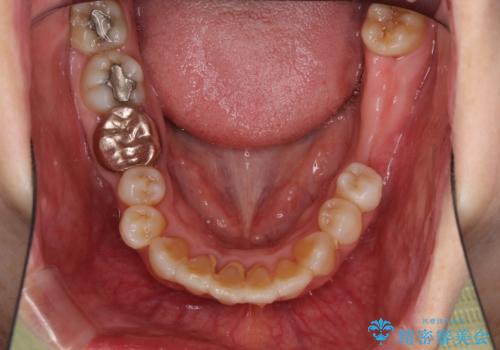

- 歯の欠損や歯肉からの出血などを気にして来院された患者様です。

診査の結果、歯周病であることが分かり、抜歯が必要な歯も見受けられました。

骨造成やインプラント、歯周外科、歯肉移植、矯正など、多くの処置を組み合わせて治療を行うこととしました。